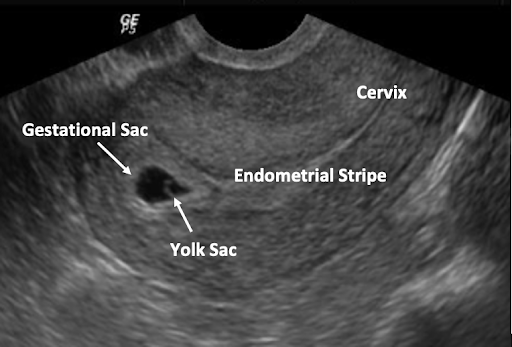

- Use longitudinal view to confirm IUP by ensuring that the gestational sac is contiguous with the endometrial stripe. Place the probe marker up (12 o’clock) and scan the uterus side to side to its most lateral aspects (ovaries may or may not be lateral to the uterus). View shows uterine fundus above the cervix with pregnancy inside. Picture below demonstrates an anteverted uterus (fundus on left) with intrauterine pregnancy. Fundus will be on the right side of the screen with a retroverted uterus.

(Images AIUM Image Library: Obstetrics 2018)

The Gestational Sac (GS)

- GS is the first evidence of pregnancy on US, as early as 4.5 weeks LMP; should always be seen by 5 weeks 5 days LMP by TVUS (Barnhart 2012).

- Although gestational sac cannot definitively be diagnosed until a yolk sac or embryo is seen (Richardson 2015), an intrauterine fluid collection is a probable IUP if there are certain US features and no adnexal masses (Benson 2013, Phillips 2020).

- A true GS should be located in the uterine fundus, be eccentric (not midline) to endometrial canal, be round (or oval) in shape, and have a decidual reaction, demonstrating the FEEDS mnemonic.

The Yolk Sac (YS)

The YS is the first single US finding that confirms an IUP. The YS is a round echoic ring with an anechoic (dark) center seen within GS. It appears typically at 5 1/2 weeks when the MSD is 5-10 mm. A YS should not be included when taking a measurement of the embryo. The size of the YS is not diagnostic.